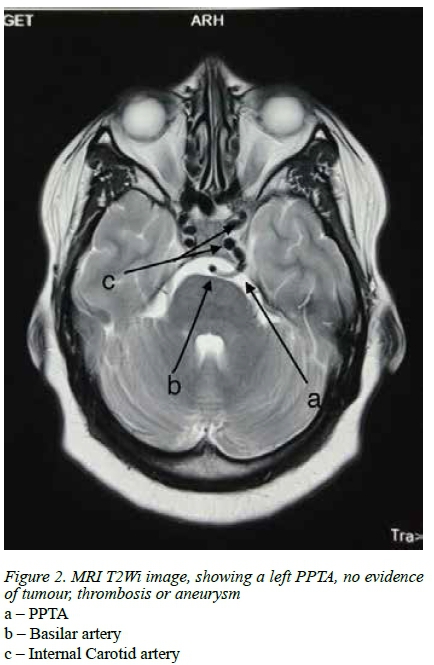

On presentation she was afebrile with a blood pressure of 150/105 mmHg a pulse rate 64 beats per minute and respiratory rate of 16 breaths per minute. She was fully conscious and cooperative. She had a left sided ptosis (Figure 1), decreased movement of the left eye in all directions, diplopia and decreased sensation to soft touch and pin prick over the left forehead and maxilla. Sensation over the mandible was distinctly spared. These signs were consistent with a fallout of the left cranial nerves, III (Oculomotor), IV (Trochlear), VI (Abducens), V1 (Ophthalmic branch of Trigeminal) and V2 (Maxillary branch of Trigeminal), all of which pointed to a lesion in the left cavernous sinus. Biochemical tests urea and creatinine, full blood count and cerebrospinal fluid chemistry were all normal. MRI revealed a PPTA (Figure 2).

MRA confirms this and suggested an absent PCommA (Figure 3).